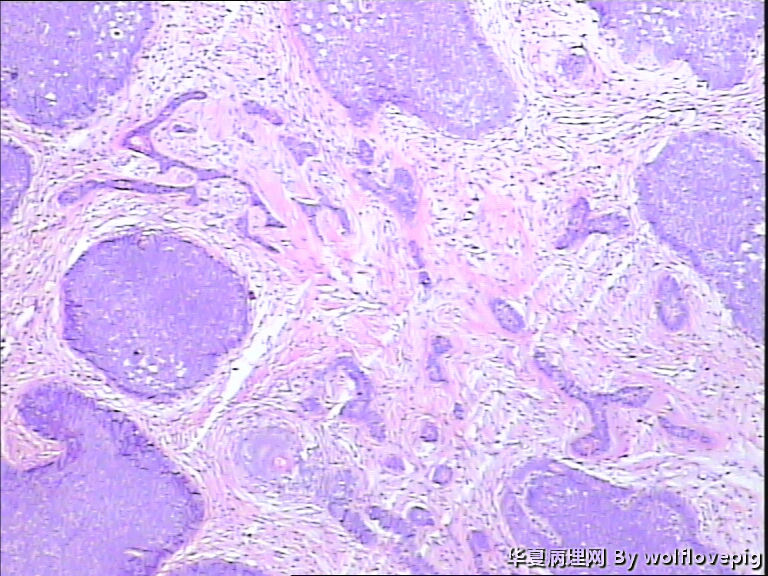

女,58y,右面部包块10年。灰白不整形带皮组织一块:2.3cm*1.5cm*0.3cm,切面有一灰白区域,质软,边界欠清。

图1

诊断考虑毛母细胞瘤,或毛发上皮瘤。

没有基底样物质,没有收缩裂隙,细胞异型不大,无明确核分裂像,考虑:附属器肿瘤,有点像汗腺来源的,如真皮导管瘤或螺旋瘤。请老师指点。

与表皮无关,表皮无破溃,无收缩间隙-------不支持BCC  有角囊肿 促纤维增生-----支持毛发上皮瘤